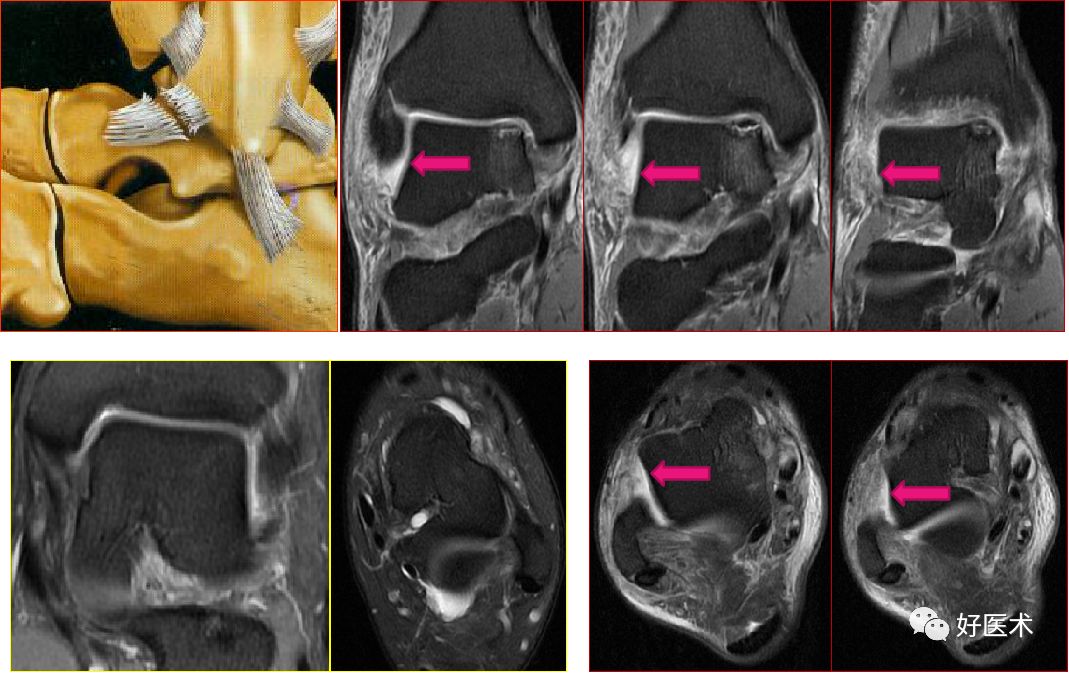

联合韧带

胫腓前后韧带:位于胫距关节上方,连接外踝前、后面与胫骨前、后结节,起支持作用

胫腓横韧带:位于胫腓后韧带前下方,后外踝延伸至胫骨关节面后缘,恰好位于内踝的外侧

联合韧带(胫腓前韧带)撕裂